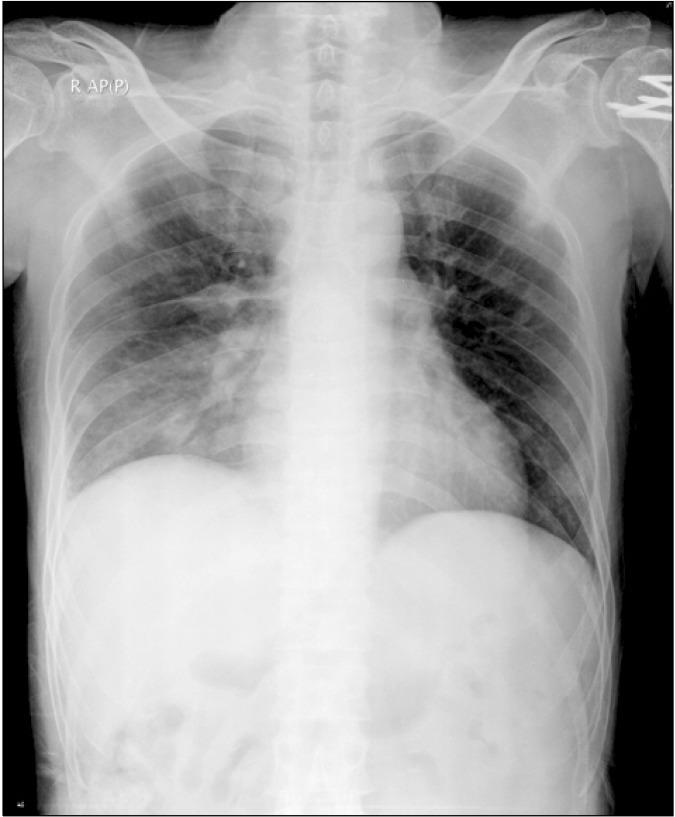

A Septic embolism is a type of embolism infected with bacteria containing pus. These may become dangerous if dislodged from their original location. Embolisms of this type in the azygos vein are potentially fatal. The diagnosis of septic azygos vein embolism is difficult, so rapid diagnosis and treatment is important to avoid complications. Generally, treatment is enough for appropriate antibiotic therapy without anticoagulant therapy. We report a case of staphylococcal septic embolism in the azygos vein, which was discovered in a 51-year-old man exhibiting chest pain, dyspnea and fever. The patient was treated with antibiotic therapy alone without the use of anticoagulants.

脓毒性栓子是一种被含有脓液的细菌感染的栓子。如果这些栓子从其原来的位置脱落,可能会变得危险。奇静脉中的这种类型的栓子有潜在致命性。脓毒性奇静脉栓子的诊断很困难,因此快速诊断和治疗对于避免并发症很重要。一般来说,适当的抗生素治疗就足够了,无需抗凝治疗。我们报告一例奇静脉葡萄球菌脓毒性栓子病例,该病例是在一名出现胸痛、呼吸困难和发热的51岁男性中发现的。该患者仅接受了抗生素治疗,未使用抗凝剂。